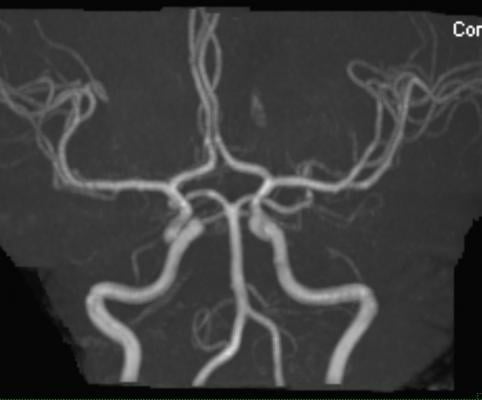

Whole-body MRA allows clinicians to take a broader view of the vascular system.

“The key advantages of this MRA technique include the ‘whole-body’ approach, which detects systemic disease that would be missed by modalities assessing single vascular sites,” said study co-author Graeme Houston, M.D., from the University of Dundee in Dundee, Scotland. “The results offer a validated quantitative score of atherosclerotic burden, and the technique does not use ionizing radiation, which is an advantage over CT [computed tomography] angiography.”

Houston and colleagues used whole-body MRA to quantify the burden and distribution of asymptomatic atherosclerosis in 1,513 people, average age 53.5 years old. The participants were considered in the low-intermediate risk group, with a 10-year cardiovascular disease risk of less than 20 percent. The researchers assessed 31 arterial segments in each participant.

With whole-body MRA, the researchers were able to detect early atherosclerotic disease throughout the body, disease that would have been missed by methods that evaluate only a single vascular territory. The technique’s high technical success rate — researchers were able to interpret 99.4 percent of the potentially analyzable arterial segments — underscores its potential for more widespread use.